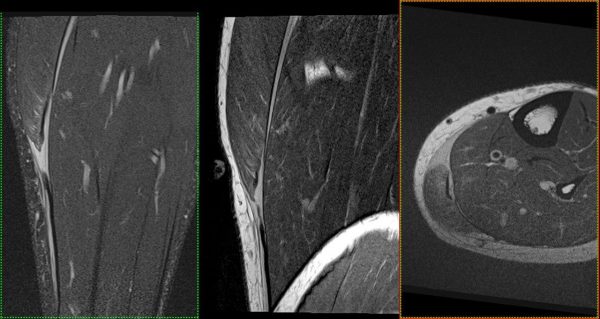

- МРТ: Створює найчіткіші зображення м’яких тканин, органів та судин. Без використання шкідливого випромінювання, тому також підходить для візуалізації вагітних, дослідженні плоду.

У нас є можливість проведення досліджень високої роздільної здатності всіх органів та систем (за винятком серця), зокрема в складі синдромів/комбінованих вадах. Обстеження виконуються, як для дітей так і дорослих пацієнтів, в т.ч. з анестезіологічним забезпеченням (седація, наркоз).

Завдяки передовим технологіям ми маємо можливість проводити МРТ дослідження “всього тіла” (whole body)*, мультипараметричні обстеження головного мозку та простати з наявними програмами МР-трактографії (DTI), МР-спектроскопії, також виконуємо безконтрастну МР-ангіографію інтракраніальних судин, шиї; МР-холангіопанкреатографію, ентерографію, визначення перенавантаження залізом печінки.